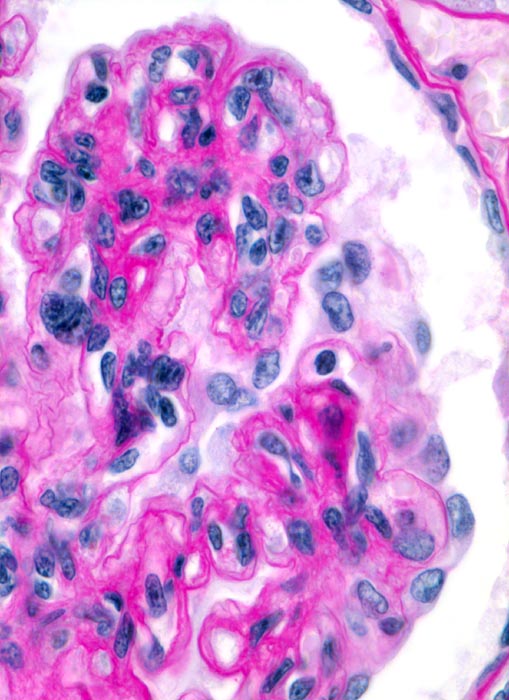

Morphologisch handelt es sich bei der membrano-proliferativen Glomerulonephritis um eine durch Mesangium- und Kapillarwandschädigungen charakterisierte Immunkomplexglomerulonephritis (Synonym: mesangiokapilläre Glomerulonephritis). Man unterscheidet einen Typ I mit subendothelialen Depots (> 2696) von einem Typ II mit dichten intramembranösen Ablagerungen (besser als intramembranöse Glomerulonephritis oder dense deposit disease bezeichnet) (> 2264).

Die Erkrankung läuft phasenhaft ab (> 2630): initial subendotheliale Depots begleitet von neutrophilen Granulozyten und Monozyten in den Schlingenlumina (> 2636), später mesangiale Zellvermehrung, Auswandern in die Schlingenperipherie (mesangiale Interposition) und subendotheliale Basalmembranneubildung (Tramgleisbild aufgrund einer Basalmembranverdopplung). Schliesslich Abnahme der subendothelialen Depots und zunehmende mesangiale Matrixvermehrung zum Teil mit knotiger Umwandlung der Mesangiumfelder.

Immunhistochemisch primär subendotheliale (> 2696), später auch mesangiale granuläre Depots reich and Komplement C3 (> 2667), daneben meist auch IgG, IgM und IgA.

Elektronenmikroskopisch hauptsächlich subendotheliale, später auch mesangiale (> 2690) und gelegentlich einzelne subepitheliale Depots.